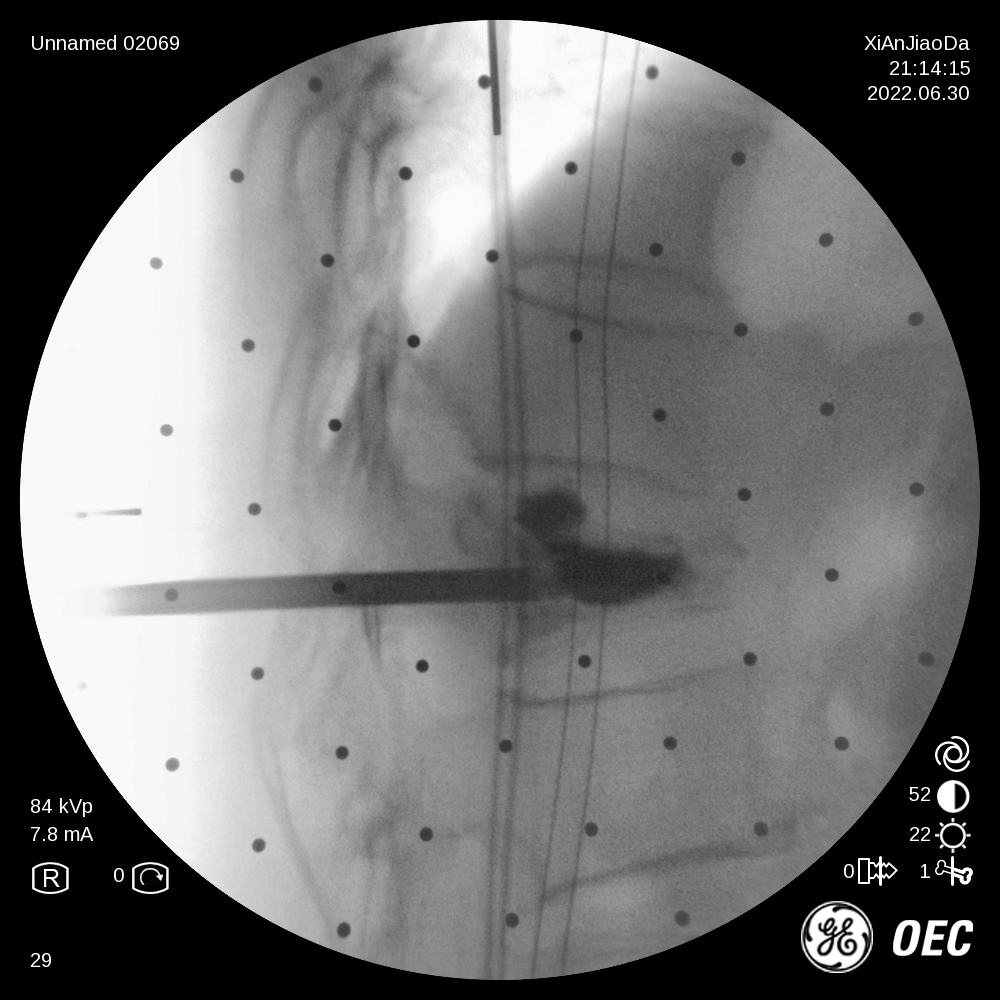

在该机器人辅助手术过程中,仅需通过正侧位进行伤椎识别,通过软件将正侧位透视图与术前规划数据的结合,即可得到病人伤椎的姿态以及实际的穿刺角度,之后机械臂根据软件参数进行精准定位,手术医生在机械臂引导下一次性进针成功,并对进针位置角度表示满意,整个过程少于20分钟,实现了手术的更精准化、高效化。相较于传统定位流程,术前规划只能保存在医生脑海中,术前与术中流程无法很好的衔接,术中穿刺依赖医生丰富的经验,对于情况复杂的病人,术中需要反复试验,导致手术时间延长、患者受辐射量增加。后续放置球囊、注入骨水泥等操作则同传统手工操作。